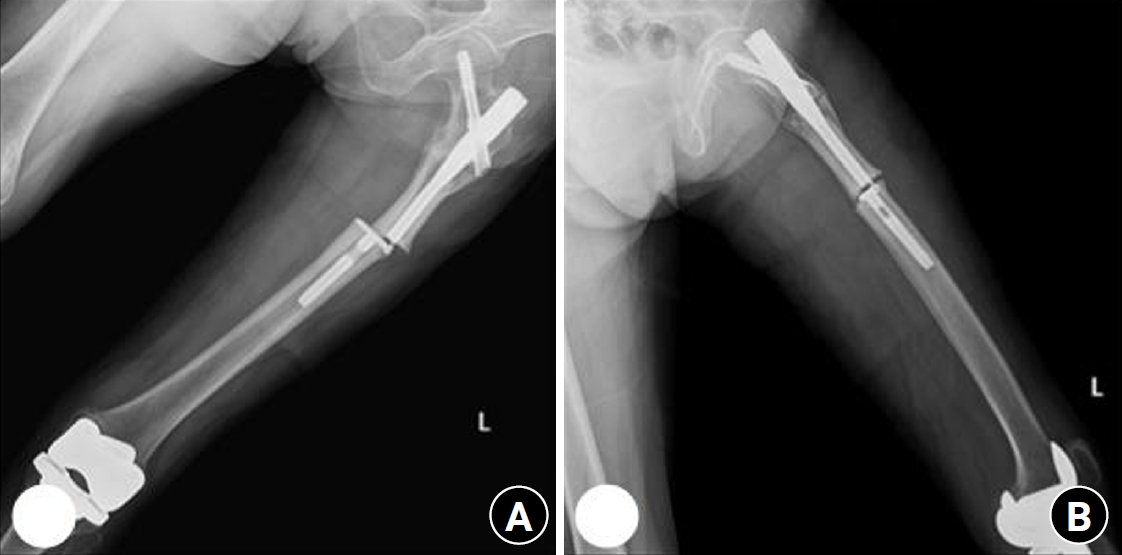

Fig. 2.

Radiograph obtained 3 years earlier of a 58-year-old female patient presenting with a right subtrochanteric femoral fracture (anteroposterior view).

Case 1: synostosis of hip joint

A 58-year-old female patient visited our emergency room, complaining of pain in the right hip that occurred the day before her hospital visit. She had a history of restricted right hip range of movement following a dislocation of the right hip in her youth, and she typically walked with a cane. The day prior to her visit, while lying on her right side and sleeping, she developed pain in the right hip area without any history of trauma. Upon examination, the patient had a background of hypertension and exhibited a bone mineral density (BMD) of ‒0.1 in the femoral neck. Notably, she had no history of malignancy. Initial physical examination and computed tomography scans conducted upon her arrival did not reveal any signs of malignancy or infection at the fracture site, indicating a low likelihood of these conditions as contributing factors. Radiographic evaluations, including both hip anteroposterior and right axial views, demonstrated signs of synostosis involving the right femoral head and acetabulum. A fracture was observed in the subtrochanteric area of the right femur, characterized by a beak-shaped thickened cortex on the lateral side of the fracture site. Importantly, the radiographs obtained 3 years prior showed no abnormalities at the fracture site (Figs. 2, 3). Following the diagnosis, the patient underwent open reduction and internal fixation using a plate. Subsequent follow-up indicated successful bone union at the fracture site.